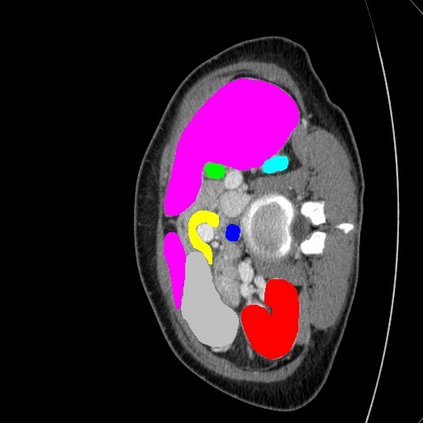

Transformers have made remarkable progress towards modeling long-range dependencies within the medical image analysis domain. However, current transformer-based models suffer from several disadvantages: (1) existing methods fail to capture the important features of the images due to the naive tokenization scheme; (2) the models suffer from information loss because they only consider single-scale feature representations; and (3) the segmentation label maps generated by the models are not accurate enough without considering rich semantic contexts and anatomical textures. In this work, we present CASTformer, a novel type of generative adversarial transformers, for 2D medical image segmentation. First, we take advantage of the pyramid structure to construct multi-scale representations and handle multi-scale variations. We then design a novel class-aware transformer module to better learn the discriminative regions of objects with semantic structures. Lastly, we utilize an adversarial training strategy that boosts segmentation accuracy and correspondingly allows a transformer-based discriminator to capture high-level semantically correlated contents and low-level anatomical features. Our experiments demonstrate that CASTformer dramatically outperforms previous state-of-the-art transformer-based approaches on three benchmarks, obtaining 2.54%-5.88% absolute improvements in Dice over previous models. Further qualitative experiments provide a more detailed picture of the model's inner workings, shed light on the challenges in improved transparency, and demonstrate that transfer learning can greatly improve performance and reduce the size of medical image datasets in training, making CASTformer a strong starting point for downstream medical image analysis tasks.